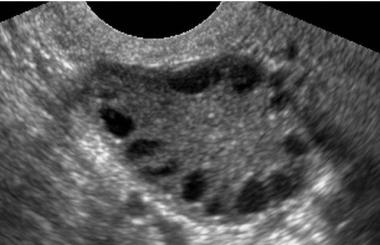

Yukardaki resimde polikistik over sendrom olan bir kişinin yapılan ultrasonunda yumurtalığındaki küçük kistler izlenmektedir.

Ultrasonda yumurtalıkta hastalığa özgü 2-9 mm çapını geçmeyen bir çok sayıda kist ile ovulasyon yani yumurtlamanın olmaması izlenir. Yumurtlamanın olmamasına "anovulasyon" denir.

Ayrıca yumurtalıkların hacmi de normale göre artmıştır, yani yumurtalıklar normalden daha iri görünüdedir.